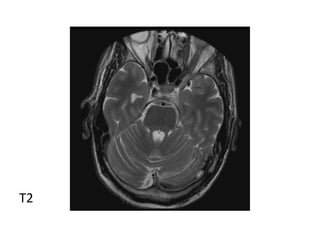

T2 of acute infarct with increased signal involving the right

putamen and body and superior head of the caudate sparing

the inferior caudate and globus pallidus

(Left) T2 and diffusion (Right) showing bilateral thalamic infarcts